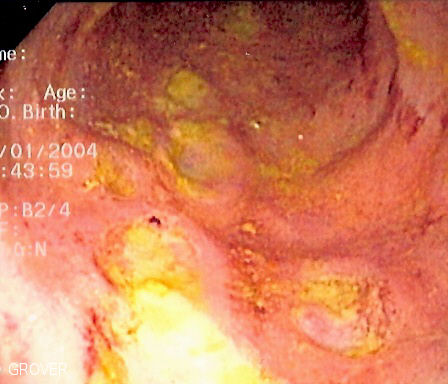

English: Endoscopic image of Crohn's colitis showing deep ulceration in sigmoid colon.